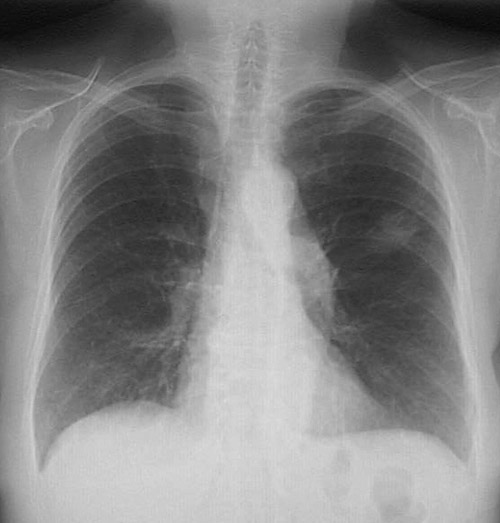

A peripheral adenocarcinoma of the lung appears in this chest radiograph of an elderly woman. She was a non-smoker. Lung cancers in non-smokers are rare, but if they occur, they are likely to be adenocarcinomas.